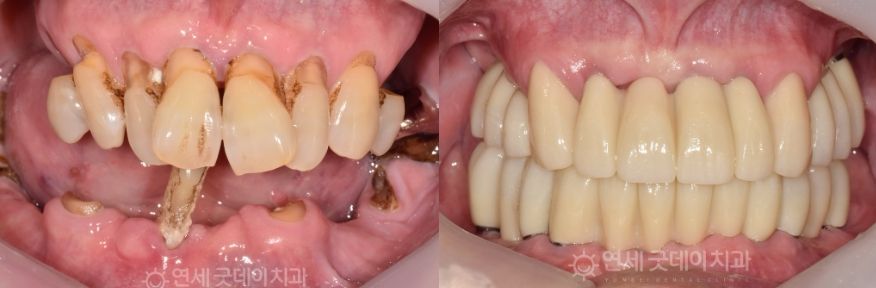

Case Review

Full Mouth Implant Before & After